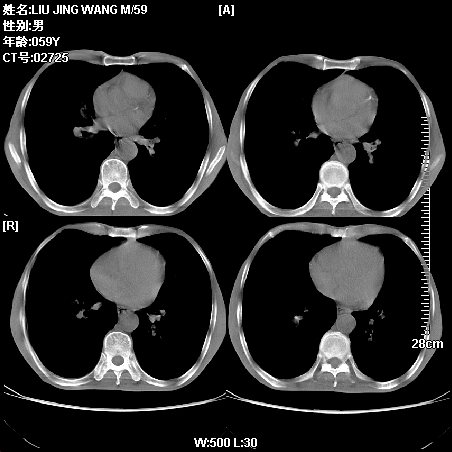

肿瘤科住院病人,都有食管癌史,都有放化疗治疗,两下肺病变是转移灶?还是其他原因造成?请老师指点

病例一 现呼吸困难,经抢救多次,咳嗽咳痰,发现食管癌2个多月

第一个病例我感觉不是转移,第二个是个放射性肺炎;但两个都有纵隔淋巴结肿大,以第二个为主;请楼主参考

符合放射性肺炎,第一例不除外坠积效应